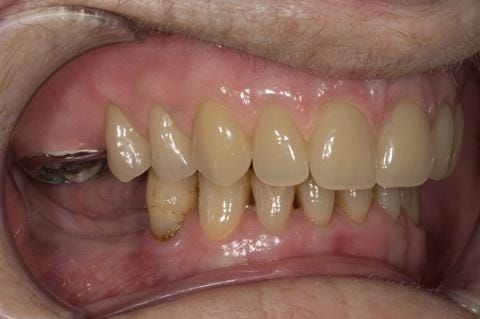

- Poorly fitting cobalt chromium based maxillary partial denture, which has been added to. This exhibited poor retention, stability and tissue fit (support). Unable to wear a new acrylic based denture.

- UR7 - occlusal amalgam. 10- 20% alveolar bone loss. Healthy periodontium with reduced attachment level. No mobility.

Following consultation and second discussion appointment the patient chose to have option 2 namely, a window denture - maxillary cobalt chromium based partial denture. The clinical situation and treatment process is shown in detail below with photographs. The patient was successfully rehabilitated with this and her quality of life considerably improved. The clinical work was provided by Finlay and the technical work by Rowan.